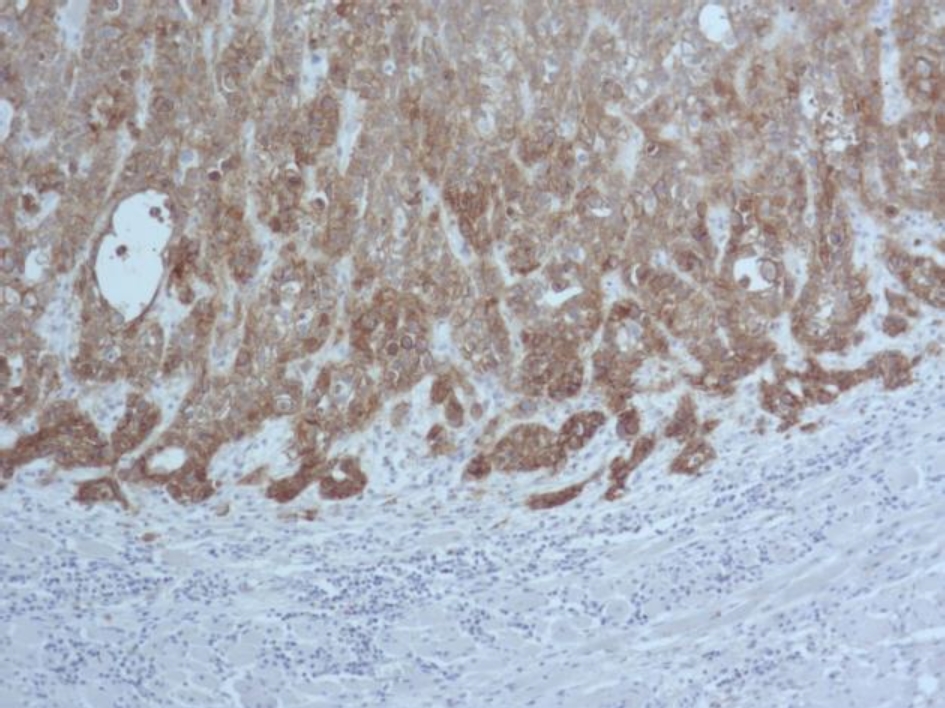

Во всех 19 исследуемых наблюдениях проведено дополнительное параллельное иммуногистохимическое исследование по выявлению экспрессии белков EGFR и Cyclin D1 соответственно, при этом диффузная, преимущественно умеренная экспрессия EGFR опреде-лялась в 17 (89 %) из 19 наблюдений (рис. 3), очаговая слабая экспрессия – в двух наблюдениях (11 %).

Экспрессия Cyclin D1 всех анализируемых наблюдений была очаговой, слабой и умеренной (рис. 4).

Рис. 3. Диффузная экспрессия EGFR в клетках плоскоклеточного рака языка. ИГХ окрашивание, ×100

В нашем исследовании в 100 % наблюдений с амплификацией гена EGFR выявлена экспрессия белка EGFR, однако в 89 % экспрессия была сильной, а в 11 % наблюдений – умеренной. Исследователями также в 100 % наблюдений рака языка выявлено соответствие между амплификацией гена EGFR и экспрессией белка EGFR, однако наблюдения с высоким количеством копий EGFR сопровождались более интенсивной экспрессией белка EGFR при иммуногистохимическом исследовании. Мы не выявили такой закономерности.